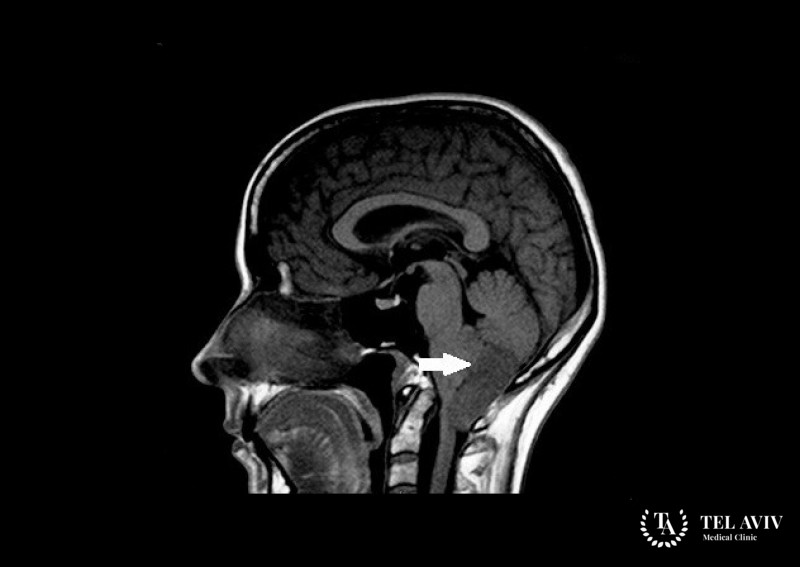

- МРТ или КТ;